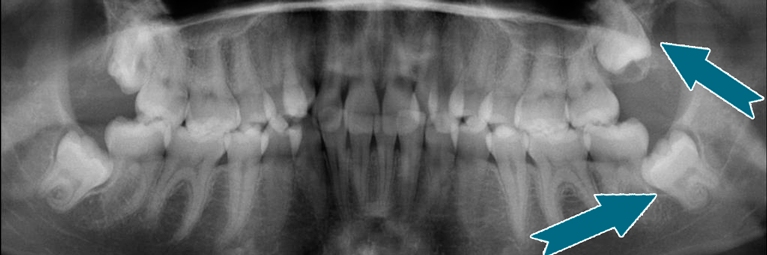

De fleste får opereret eller trukket visdomstænderne ud.